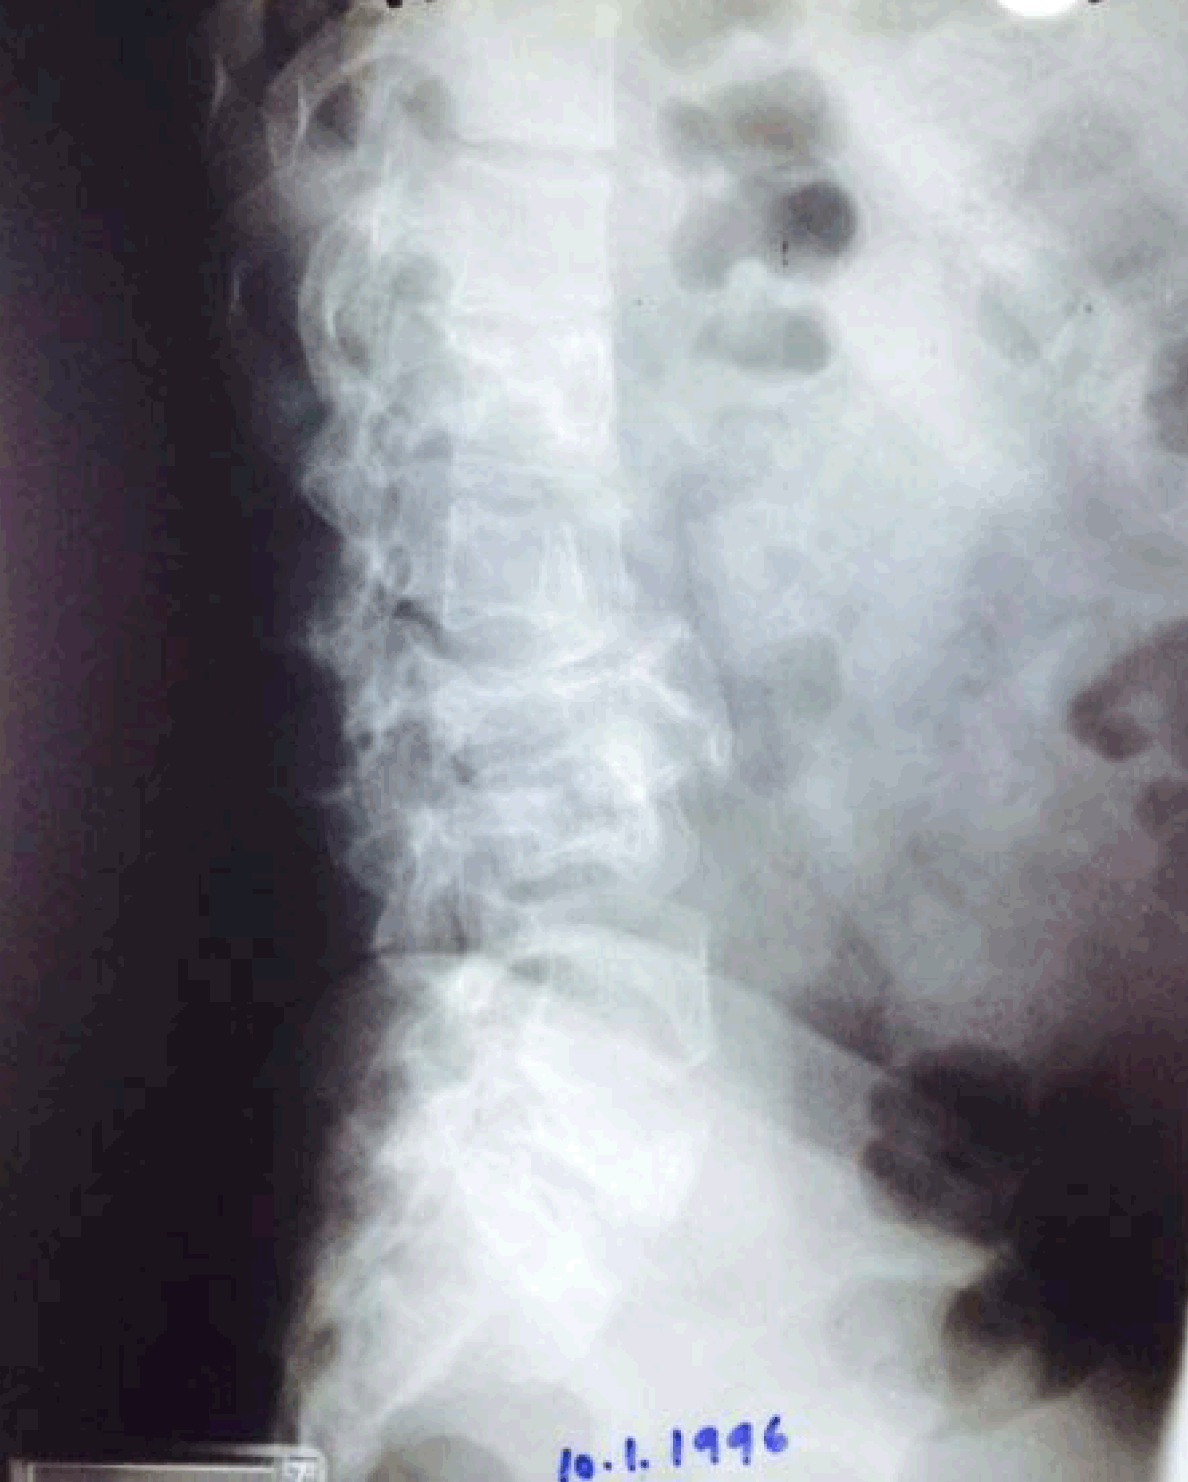

On enquiry, the patient produced an old set of Lumbar spine radiographs taken three years back for the same complaints, which revealed almost the same radiographic findings (Figure 2).

Figure 2: X-ray dorsolumbar spine lateral view taken three years back showing the same radiographic features without much change.